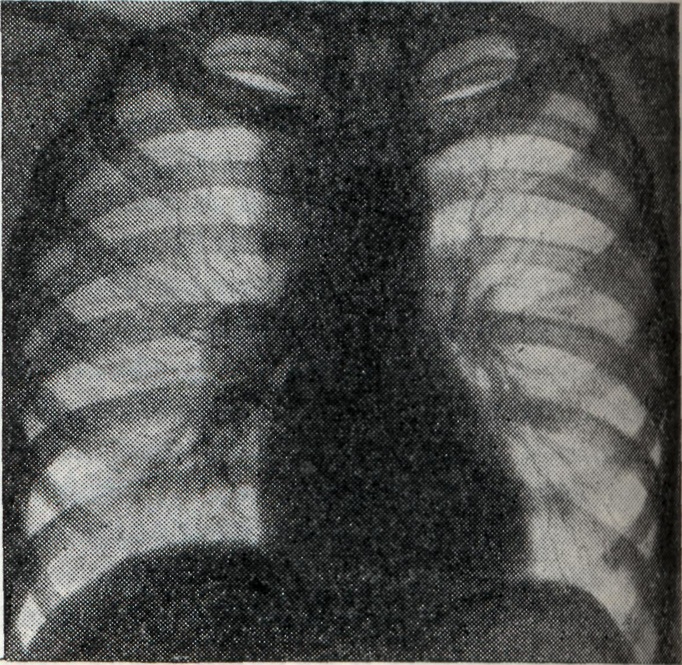

Бронхагенное рассеивание казеозного материала ведёт к развитию тяжёлых бронхопневмоний (лобулярио-казеозных). Осложнения. Течение Б. нередко осложняется плевритом (железисто-плевральный синдром); характерны междолевые экссудативные плевриты (чаще при первичном туберкулёзе). При большом увеличении группы лимф, узлов может возникнуть ателектаз сегмента или доли лёгкого. Длительное существование ателектазов может привести к фибротизации спавшегося участка с образованием бронхоэктазов. Диагноз ставится на основании комплексного клинико-рентгенологического обследования, анамнеза (контакта с туберкулёзным больным), характера туберкулёзной интоксикации. Подтверждением туберкулёзной этиологии процесса в висцеральных грудных лимф, узлах является туберкулиновая проба (см. Туберкулинокагностика). При туберкулёзном Б. чаще встречается резко положительная туберкулиновая проба. При туберкулёзном Б. с тяжёлым осложнённым течением туберкулиновые пробы могут быть слабоположительными (состояние анергии). Выявлению клинически не диагностируемых и осложнённых форм Б. способствует также бронхоскопия (см.), при к-рой нередко обнаруживаются инфильтративные изменения стенки бронха и свищи соответственно расположению патологически изменённого лимф. узла. Основной метод диагностики Б. — рентгенологический. Рентгенодиагностика имеет целью установить наличие увеличенных или уплотнённых висцеральных грудных лимф, узлов. При этом руководствуются принципом целенаправленного рентгенологического исследования области средостения путем применения различных способов послойной рентгенографии (томография лучами повышенной жесткости с продольным, поперечным и косым направлением размазывания теней, с выделением толстых слоев — зонография). Послойная рентгенография должна быть многопроекционной (см. Полипозиционное исследование). Особенно ценнов диагностике поражений труднодоступных для выявления групп лимф. узлов (бифуркационных, левых трахео-бронхиальных, парааортальных, артериального протока, бронхо-пульмональных) использование не только прямых и боковых, но и косых проекций с поворотом грудной клетки на 45° в правом и левом лопаточном положении. На послойных рентгенограммах выявляются сочетанные поражения бронхов и лимф, узлов, а в отдельных случаях — лимфо-бронхиальные свищи и компрессионные стенозы. При опухолевидной форме Б. перифокальные явления в прилегающей лёгочной ткани обычно отсутствуют. Тень корня увеличена, менее структурна, отдельные сосудистые стволы корня плохо различимы (рис. 1). Проекции бронхов менее отчётливы, тень корня почти сливается с тенью средостения. Наружная волнообразная или бугристая граница деформированного корня проецируется в виде отчётливой, хотя и не всегда резкой линии, что зависит от отсутствия или наличия воспалительных изменений в капсуле лимф, узлов. При одностороннем опухолевидном Б. изменения корня противоположного лёгкого менее выражены (рис. 2), на стороне поражения лёгочный рисунок несколько усилен, прилежащие листки междолевой плевры уплотнены (рис. 3). При вовлечении в процесс медиастинальной плевры бугристые наружные контуры корня или средостения могут исчезать. Тень средостения расширена, имеет гладкие контуры.

При инфильтративной форме Б. (рис. 4, 1 и 2) возникают воспалительные изменения в лёгочной ткани за капсулой лимф, узлов. Поэтому весь корень или отдельные его участки увеличиваются, тень корня уплотняется. Линия наружного контура корня делается неясной и размытой от воспалительного уплотнения перибронхиальной, периваскулярной и межуточной ткани лёгкого. Опухолевидная и инфильтративная формы Б. при благоприятном течении процесса заканчиваются Рубцовым уплотнением корней лёгких (рис. 5); в отдельных группах лимф, узлов наблюдаются и явления кальцинации (петрификаты): отдельные мелкие плотные тени, иногда сгруппированные в более крупные конгломераты. Дифференцирование сосудистой тени от кальцинатов в лимф, узле проводится при многоосевом просвечивании: тень от петрификата в корне легкого при поворотах исследуемого не выходит за его границы, интенсивность ее не изменяется; тень от осевой проекции сосуда при движении больного вытягивается вначале в овал, а затем в продольную линейную проекцию. Кроме того, тени кальцинированных лимф, узлов редко бывают монолитно плотными и правильной округлой формы с ровными краями, что более характерно для осевых проекций сосудов. При дифференциальной диагностике Б. не следует забывать таких заболеваний, как бронхокарцинома, лимфогранулематоз (см.), лейкемия (см. Лейкозы), застойный корень, бруцеллез (см.), гиперплазия зобной железы, аневризма аорты (см.), лимфосаркома (см.). Прогноз в основном благоприятный, но течение медленное, особенно при формах с большим количеством казеоза и поражением сегментарного или долевого бронха (при образовании свищей). Лечение. В период первичного туберкулёза, когда инфекция в значительной мере генерализована, лечение должно быть направлено на укрепление всего организма с учетом степени вовлечения прилежащих органов и изменений в лёгких. Инфильтративный Б. проходит под влиянием санаторного режима. Режим больного щадящий, и лишь после исчезновения явлений интоксикации и рассасывания гиперплазированных лимф, узлов возможен переход к закаливающему режиму. Интоксикация и гиперплазия лимф, узлов быстрее проходят при применении специфических антибактериальных препаратов: изониазида (тубазид), ПАСК, стрептомицина. Как правило, назначаются сразу два препарата (для предупреждения развития лекарственной устойчивости микобактерий туберкулёза): стрептомицин + ПАСК или тубазид + ПАСК. Суточная доза стрептомицина для взрослых 0,5—1 г, тубазида 0,3—0,6 г, ПАСК 9 — 12 г. Курс лечения ок.6 мес. Казеозные Б. требуют длительного лечения в стационаре. Основной метод лечения — специфическая химиотерапия. В казеозные массы, лишенные сосудов и окружённые фиброзной капсулой, антибактериальные препараты проникают в малом количестве; сравнительно лучше других в казеозные массы проникает пиразинамид. Необходимо применять максимально переносимые дозы препаратов и лечение продолжать в течение многих месяцев (иногда больше года) без перерыва. Курс химиотерапии в 2—3 мес. снижает острые явления заболевания, но не предупреждает новой вспышки. Антибактериальные препараты действуют на казеозный процесс в лимф, узлах медленно, предотвращая вспышку процесса в лёгких или менингеальных оболочках. Известны случаи хирургического лечения Б. путём удаления казеозно изменённых внутригрудных лимф, узлов. Индуративный Б. также медленно поддаётся действию специфических антибактериальных препаратов, к-рые в процессе лечения комбинируются с различными стимуляторами, в первую очередь туберкулином, способным усилить воспалительную реакцию фиброзной ткани и казеоза. При применении антибактериальных препаратов отно-сительно быстро удаётся преодолеть обострение, для полного же излечения необходим значительный срок и комбинация различных методов лечения. Профилактика — см. Туберкулёз. См. также Туберкулёз органов дыхания.